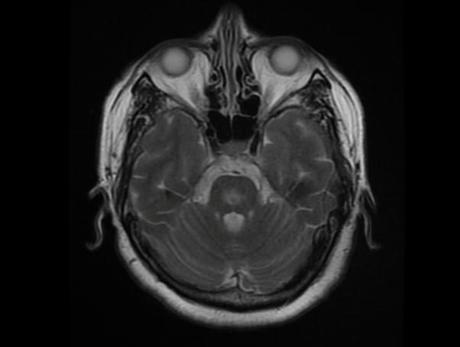

Cambios en la señal de los ganglios basales y la protuberancia, hiperintensas en Flair y con restricción en DW. Sugieren mielinolisis pontina o también llamado sind. De desmielinización osmótica, que buen caso, gracias por las imágenes

Cambios en la señal de los ganglios basales y la protuberancia, hiperintensas en Flair y con restricción en DW. Sugieren mielinolisis pontina o también llamado sind. De desmielinización osmótica, que buen caso, gracias por las imágenes

Síndrome de desmielinización osmótica con hallazgos pontinos y extrapontinos

Síndrome de desmielinización osmótica con hallazgos pontinos y extrapontinos

Mielinolisis pontina y extrapontina!

Mielinolisis pontina y extrapontina!